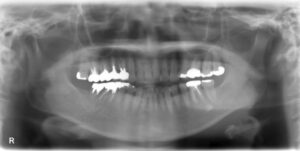

上下顎オールオン6症例

BEFORE AFTER 63歳男性/上顎6本・下顎6本 【治療内容】 全体的に歯が揺れてお食事がとりづらくなり、来院さ…